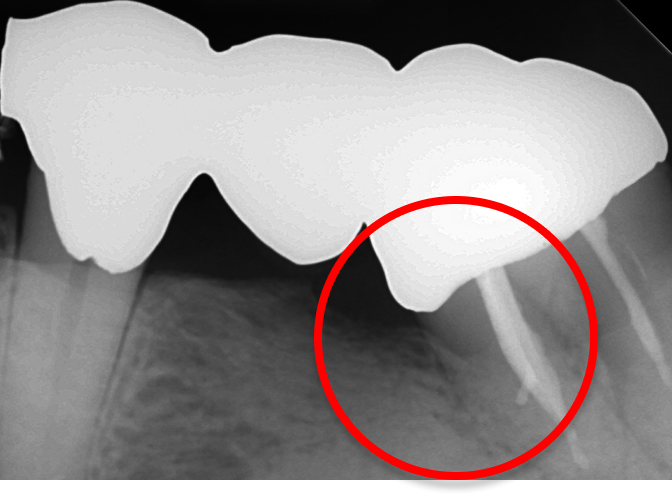

※丸印内の歯周骨が

再生されました。